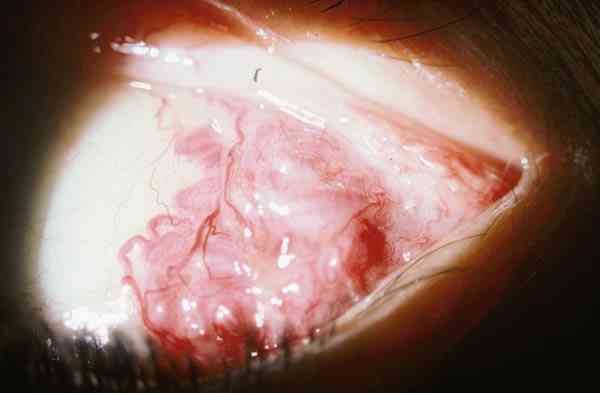

Figura 3. Infiltración leucémica subcutánea y orbitaria.

Figura 4. Las leucemias infiltran el globo ocular, nervio óptico y

órbita en varias manifestaciones.